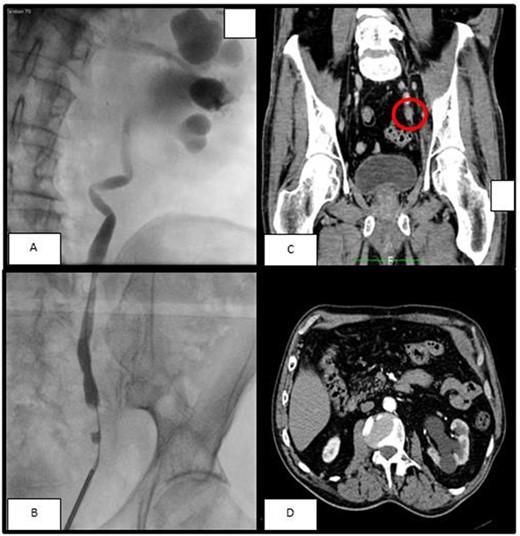

A 74-year-old man was seen for left hydronephrosis and ipsilateral lumbar pain. A contrast-enhanced abdominal computed tomography (CT) scan showed left hydroureteronephrosis with a reduction of ipsilateral renal function caused by a solid nodular formation of about 33 mm in the pelvic ureter characterized by enhancement and hyperdensity of surrounding fat (Fig. 1). So, the patient performed a positron emission tomography (PET) scan with 18-Fluorodeoxyglucose (FDG) that showed uptake of the radiopharmaceutical Standardized Uptake Value (SUV) 4.38–5.32 in the area described on the abdomen CT. Urinary cytology revealed atypical urothelial cells. Therefore, we performed a ureteroscopy with biopsy that showed a solid distal ureteral mass involving almost the entire ureteral lumen. Histological examination of biopsy revealed a malignant neoplasm.

(A, B) The retrograde pyelography, performer before ureteroscopy, showed a minus contrast at the level of the pelvic ureter with an upstream hydroureteronephrosis; (C) left ureteral mass seen at arterious CT-scan; (D) the arterious CT-scan showed a hydronephrosis with corticalization of the calyxes.